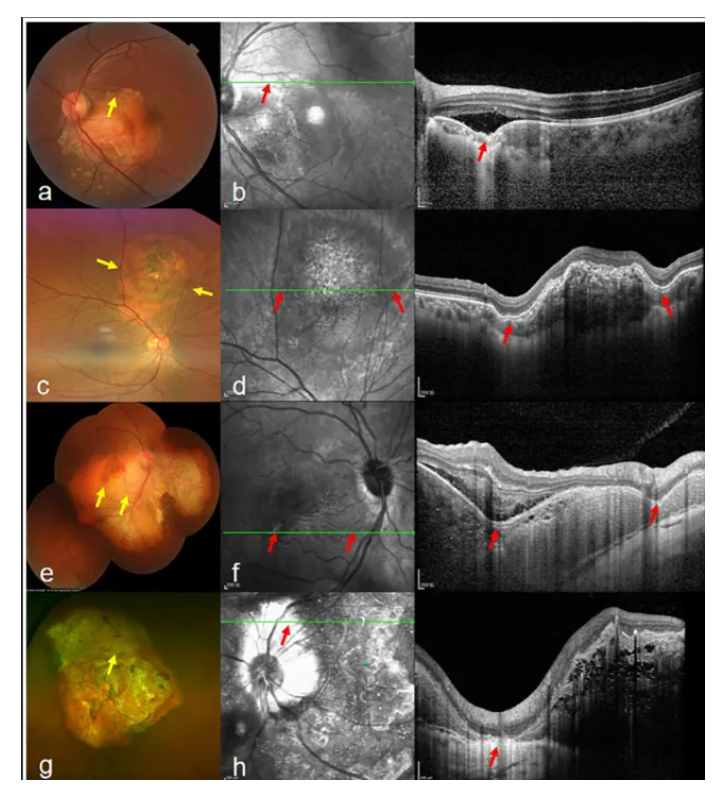

1.陈文文、蒋婷婷等人在American Journal of Ophthalmology上发表论文,首次对VRL患者光学相干断层扫描(OCT)中视网膜色素上皮(RPE)破坏性病变的成像特征和临床意义进行了系统性描述。该病变为VRL早期诊断和预后评估提供了特异性线索,并提示淋巴细胞可能通过RPE迁移的病理机制。

Chen W, Jiang T, Gu J, Liu S, Zhou X, Chang Q. Retinal pigment epithelium disruption lesions on optical coherence tomography in patients with vitreoretinal lymphoma. Am J Ophthalmol. 2025;283:100-108. doi:10.1016/j.ajo.2025.11.044